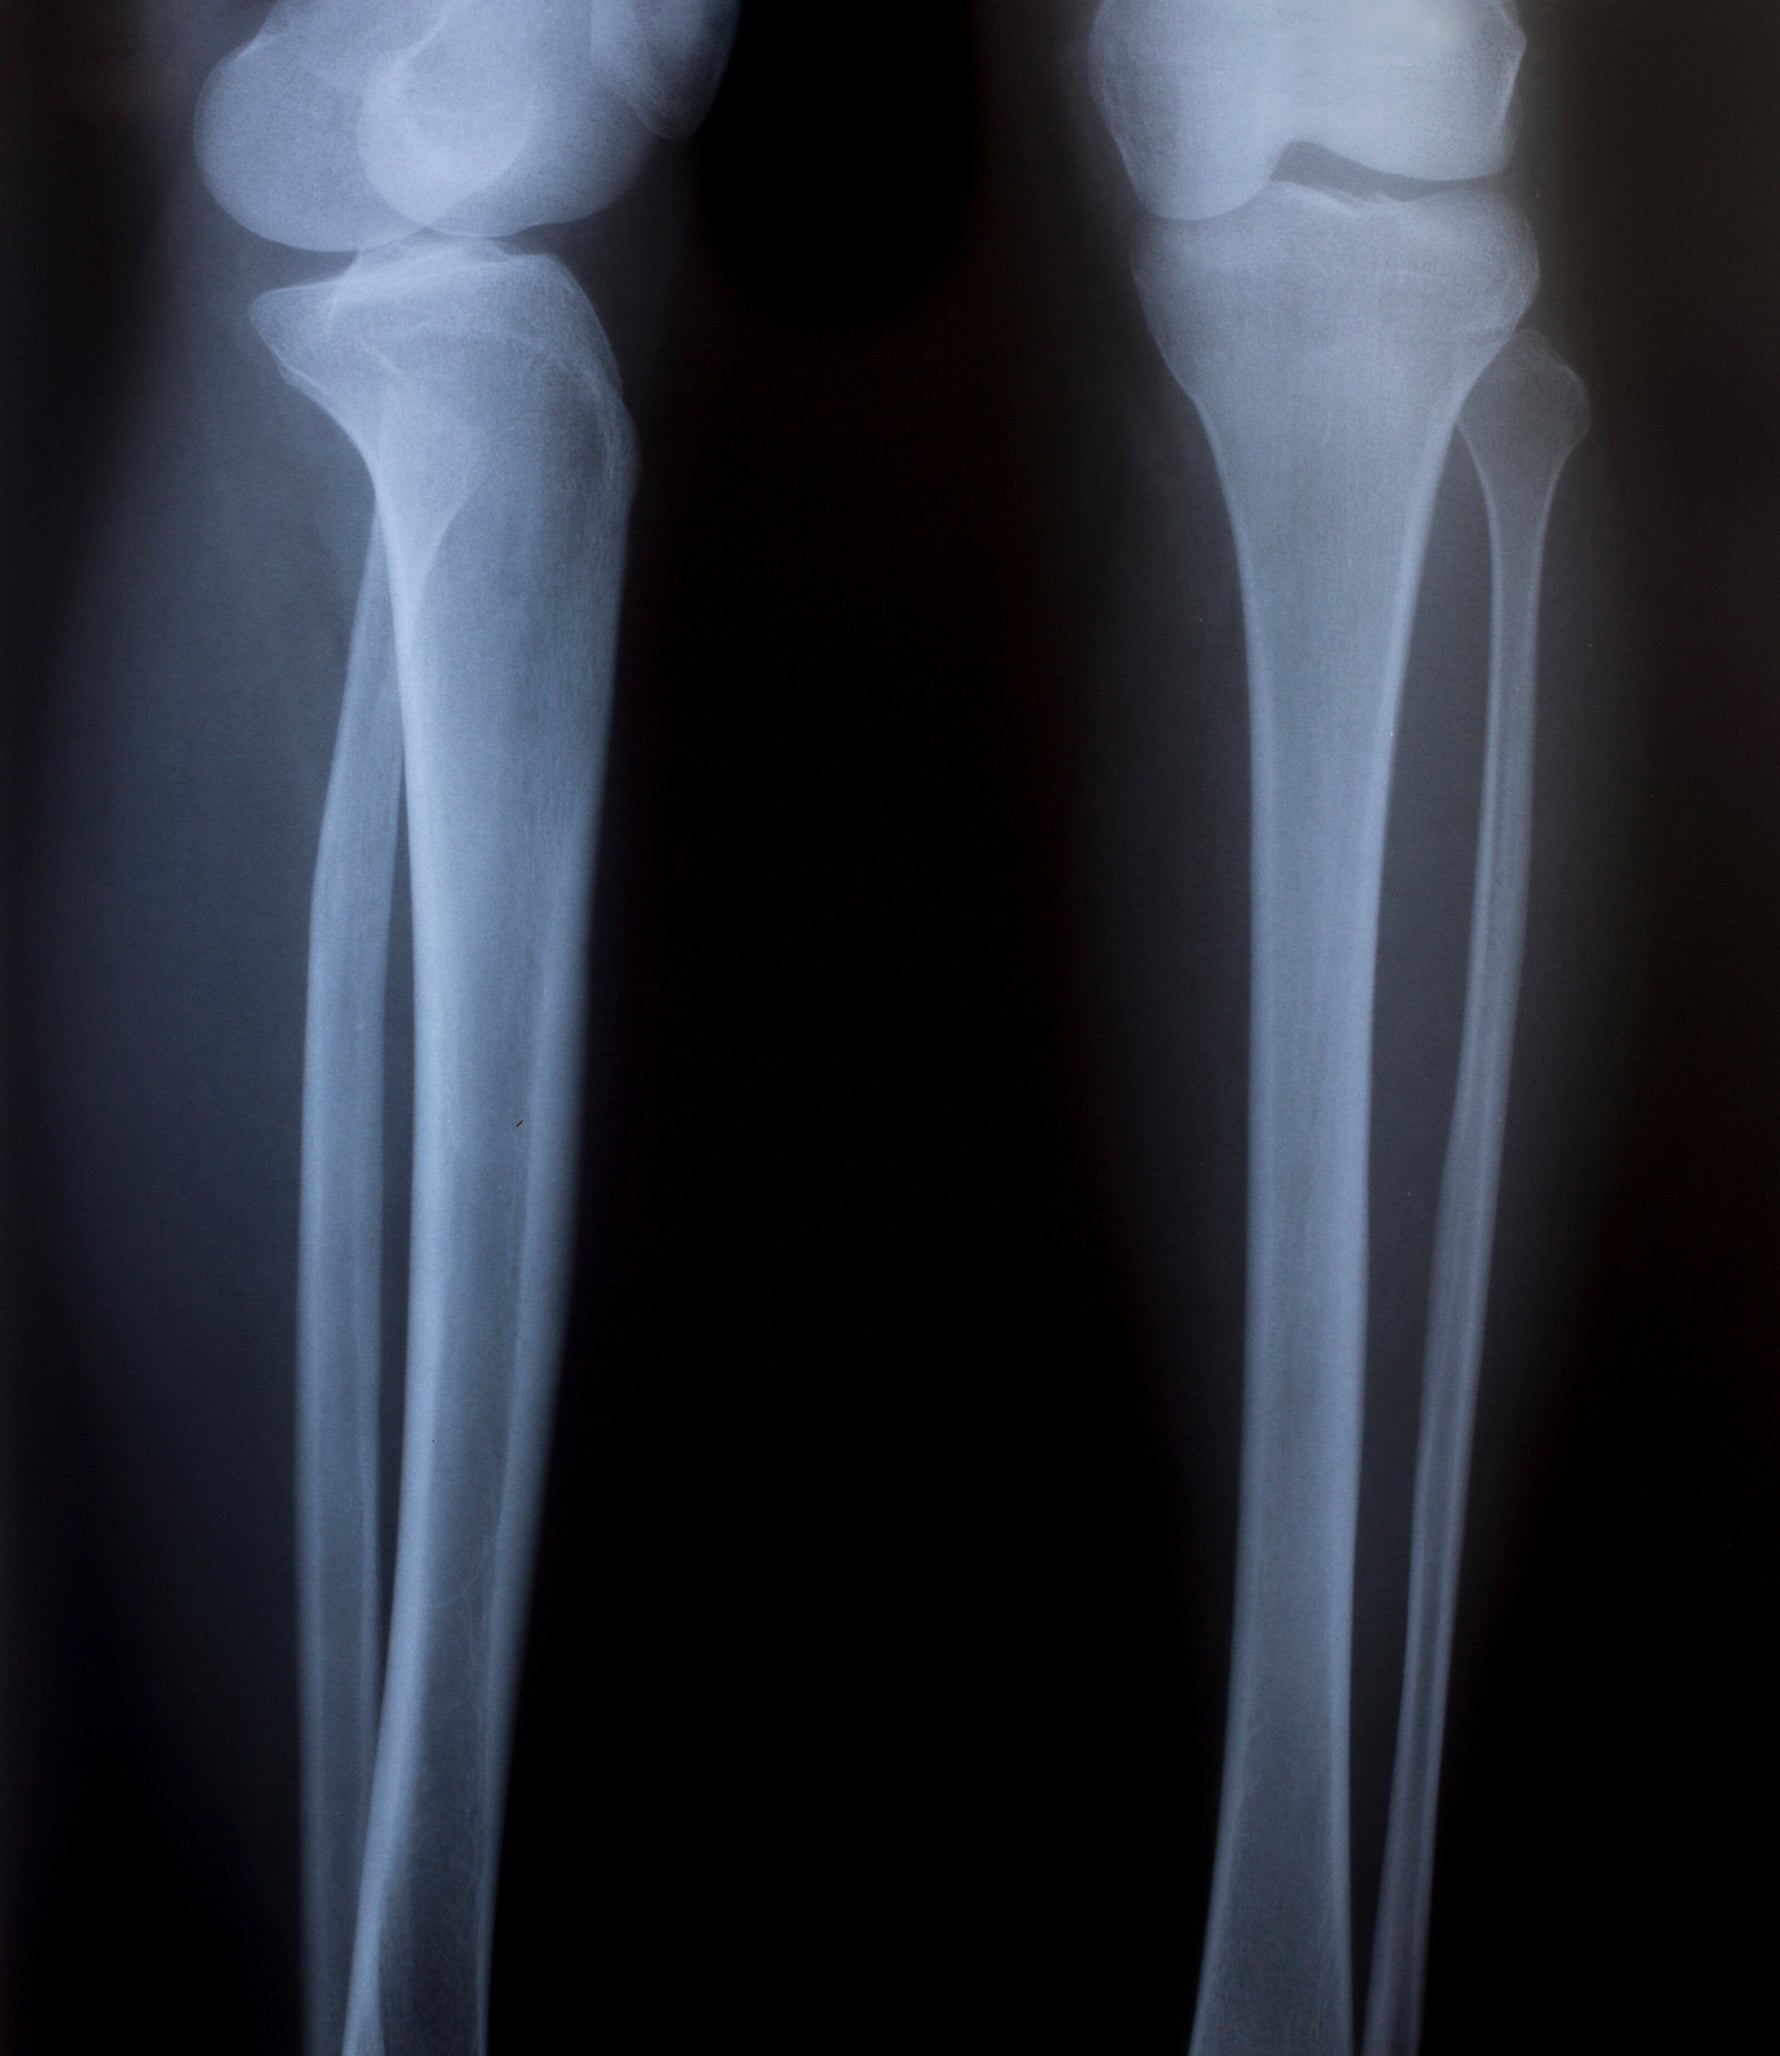

Ever wondered what lies beneath your skin? X-rays can reveal just that. During an X-ray examination, a specially trained medical professional can see exactly what your bone structure looks like and interpret what this imaging reveals. The discovery of X-rays by Wilhelm Conrad Röntgen in 1895 was a milestone that satisfied the prevailing curiosity about the interior of the human body – it allows us to literally look beneath the skin. This article by Animus Medicus brings you closer to the world of X-rays and explains what to expect during an X-ray examination. This way, you can approach your next X-ray examination with ease and learn some fascinating things about X-ray technology. What are X-rays? X-rays are a form of electromagnetic radiation, similar to the light we see or the radio waves that transmit music and news. The difference lies in their wavelength: X-rays are much shorter, which gives them the ability to penetrate certain materials, such as our bodies. X-rays were discovered accidentally by the physicist Wilhelm Conrad Röntgen, who noticed a mysterious radiation that darkened photographic plates while experimenting with cathode ray tubes. Röntgen's discovery revolutionized physics on one hand and became an indispensable tool in medical diagnostics on the other. How an X-ray machine works The function of an X-ray machine is to create an image of something that lies beneath an opaque surface. In a classic medical X-ray machine, it essentially involves a tube that shoots electrons at a piece of metal. When the electrons hit, X-rays are produced and passed through the body being examined. Since different materials absorb the rays differently, an image is created on a detector or photographic plate. Bones appear white, soft tissues in shades of gray, and air appears black. Nowadays, digital X-ray techniques can directly convert these rays into images displayed on a screen. This modernization allows for immediate assessment of the imaging by the medical professional. X-ray explained: The procedure For those who have never experienced an X-ray examination, it might be hard to imagine. Here’s how an X-ray examination typically proceeds: Preparation: When it's your turn for the X-ray, you are often first taken to a regular treatment room before entering the room with the X-ray machine. The X-ray procedure is often briefly explained to you. You may be asked to remove certain clothing items, such as medical socks for foot injuries, and change into a gown. Personal items like anatomical jewelry and piercings should also be removed before the X-ray. Safety Measures: Although X-rays in high doses can be harmful, the amounts used in a typical X-ray examination are very low. Nevertheless, lead aprons or other protective measures are used to shield body parts that are not being examined. The X-ray: An X-ray is quick and painless. You will be asked to stand or lie still while the X-ray machine is briefly activated. Your position depends on the body part being imaged. The medical staff will help you position yourself to obtain the best possible image. It is crucial to stay still during the brief moment the image is taken to ensure clarity. After the X-ray: Once the images are taken, you can get dressed and leave the room. The entire procedure often takes only a few minutes, and the results are evaluated by a radiologist, who discusses the findings with you and your treating physician. Understanding anatomy through X-rays of bones What’s remarkable about X-rays is how they reveal the hidden structures of our bodies. They enable doctors to diagnose fractures, locate foreign objects, or assess the health of joints. X-rays are not limited to the human body; they also provide insights into the anatomy of animals, which is essential for veterinary diagnoses. X-ray imaging fascinates not only medical professionals but also the general public, as it makes visible what is invisible to the naked eye. The importance of X-rays for diagnosis X-rays are often the first step in the diagnostic process. Without them, a fracture might only be guessed. The anatomical images from an X-ray can reveal conditions that are not detectable through external examination methods. These include the presence of tumors, the extent of an infection, the presence of a bone injury, or the stage of a disease. Interpreting X-ray images requires expertise, as anomalies in bones and other parts of the human anatomy are not always easy to recognize and interpret. Your specialist will explain your X-ray results in detail and recommend further treatment. X-rays beyond medicine The application of X-rays is not limited to the medical field. Here are some other fascinating areas where X-rays are used: Art and Archaeology: Analysis of artworks and archaeological finds, revealing hidden layers and previous modifications, and estimating the age of bones based on their condition. Industry: Examination of material structures and detection of flaws. X-rays can identify cracks or air pockets, allowing for the sorting out of defective materials. Security Technology: Detection and prevention of hazards, such as at airports. Objects and clothing are scanned for dangerous items. Other Fields: Geology, astronomy, and many other areas also benefit from X-ray technology. The indispensable technology of X-rays X-ray machines and their function allow us to gain deep insights into the world around us and within us. This technology has revolutionized medical diagnostics and finds applications in many other areas. Interested in anatomy and medicine? Did you enjoy this article and are interested in anatomy and medicine? Then perhaps our anatomy phone cases or anatomy pins from Animus Medicus are something for you. Visit our shop and discover our unique products!